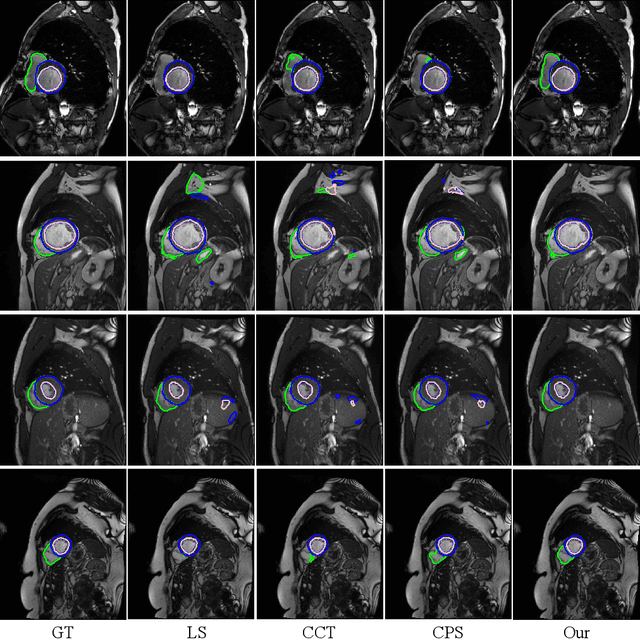

Abstract:Medical image segmentation plays an irreplaceable role in computer-assisted diagnosis, treatment planning, and following-up. Collecting and annotating a large-scale dataset is crucial to training a powerful segmentation model, but producing high-quality segmentation masks is an expensive and time-consuming procedure. Recently, weakly-supervised learning that uses sparse annotations (points, scribbles, bounding boxes) for network training has achieved encouraging performance and shown the potential for annotation cost reduction. However, due to the limited supervision signal of sparse annotations, it is still challenging to employ them for networks training directly. In this work, we propose a simple yet efficient scribble-supervised image segmentation method and apply it to cardiac MRI segmentation. Specifically, we employ a dual-branch network with one encoder and two slightly different decoders for image segmentation and dynamically mix the two decoders' predictions to generate pseudo labels for auxiliary supervision. By combining the scribble supervision and auxiliary pseudo labels supervision, the dual-branch network can efficiently learn from scribble annotations end-to-end. Experiments on the public ACDC dataset show that our method performs better than current scribble-supervised segmentation methods and also outperforms several semi-supervised segmentation methods.

Abstract:Recently, deep learning with Convolutional Neural Networks (CNNs) and Transformers has shown encouraging results in fully supervised medical image segmentation. However, it is still challenging for them to achieve good performance with limited annotations for training. In this work, we present a very simple yet efficient framework for semi-supervised medical image segmentation by introducing the cross teaching between CNN and Transformer. Specifically, we simplify the classical deep co-training from consistency regularization to cross teaching, where the prediction of a network is used as the pseudo label to supervise the other network directly end-to-end. Considering the difference in learning paradigm between CNN and Transformer, we introduce the Cross Teaching between CNN and Transformer rather than just using CNNs. Experiments on a public benchmark show that our method outperforms eight existing semi-supervised learning methods just with a simpler framework. Notably, this work may be the first attempt to combine CNN and transformer for semi-supervised medical image segmentation and achieve promising results on a public benchmark. The code will be released at: https://github.com/HiLab-git/SSL4MIS.